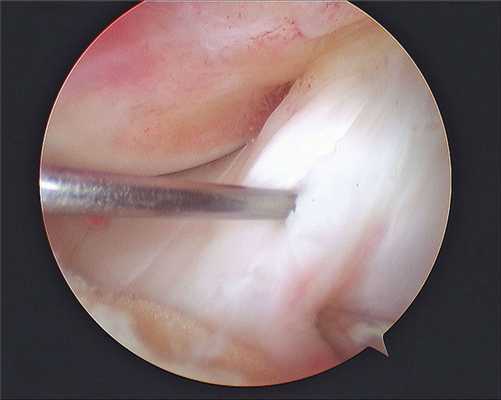

б) 30° артроскоп перемещается в нижнемедиальный порт, а в нижнелатеральный порт вводится коагулятор с крючковидной рабочей частью

в) Латеральный релиз выполняется коагулятором и начинается сразу дистальнее верхней суставной границы надколенника (рис. 7)

г) Сначала рассекаются синовиальная оболочка и капсула сустава, а затем последовательно в продольном направлении пересекается латеральный удерживатель:

• При первом проходе коагулятором рассекается капсула коленного сустава (рис. 8)

• Последующие проходы пересекают волокна удерживателя (рис. 9)

• По завершении релиза края разреза должны разойтись, что свидетельствует об адекватном релизе (рис. 10)